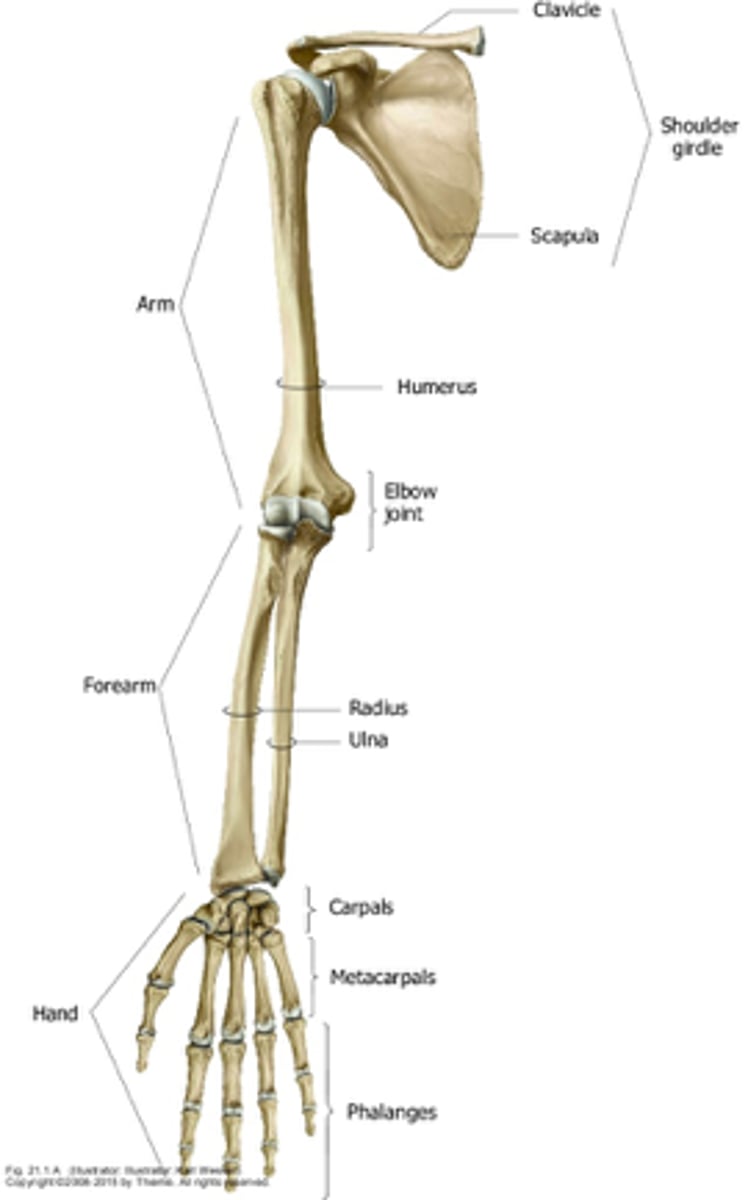

What are the anatomical divisions of the upper extremities?

- shoulder

- arm

- forearm

- hand

Overview of the Arm:

- 1st segment and longest part of the free upper limb

- extends between and connects the shoulder and elbow

Overview of the forearm:

- 2nd segment and second lomgest portion of the UL

- extends between and connects the elbow and the wrist

Overview of the hand:

- most distal

What parts consist of the hand?

- wrist

- palm

- dorsum of hand

- digits

The humerus is the ______ bone in the UE

largest

What bones do the humerus articulate with?

- scapula via glenohumeral joint

- radius & ulna via elbow joint

Bones of the forearm:

radius and ulna